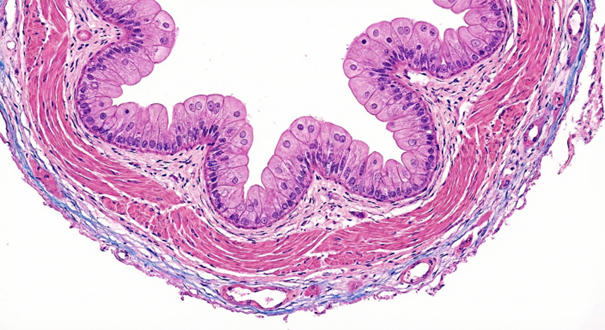

2.71 Folgende Histologische Abbildung zeigt den Querschnitt eines Hohlorgans. Um welches handelt es sich?

Antwortmöglichkeiten

• (A) Ureter

• (B) Urethra

• (C) Tuba uterina

• (D) Ductus defferens

• (E) Ösophagus